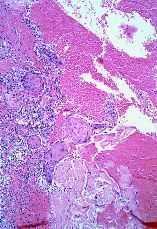

FIG. 5.--Ovillo ecrino con imágenes de SEE debajo de una úlcera reepitelizada.

FIG. 6.--Conductos con SEE localizados en tejido de granulación justamente en la incisión de la cirugía previa.